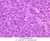

Endocrine pancreas

Although H & E staining permits ready identification of the islets of Langerhans, it does not permit differentiation of the various cell types that comprise the islets (B-36, H&E [10x, 20x, 40x-labeled]). There are no slides in the class collection that permit identification of all of the cell types of the endocrine pancreas. However, the sections on slides B-37 and B-40 permit specific identification of two cell types. Slide B-37 has been stained by the aldehyde fuchsin technique, which lends a magenta coloration to the granules of the insulin-producing B-cells. All other cells in the islets stain a dirty orange color (B-37 [10x, 20x, 40x] [10x, 20x, 40x]). Most of these orange-colored cells are the glucagon-secreting A-cells; however, you should bear in mind that somatostatin-secreting D-cells, as well as APUD cells that secrete pancreatic polypeptide are also scattered about the islet. The section on slide B-40 has been prepared by a silver impregnation method that renders some of the APUD cells in the islets (which appear as “clear cells” in ordinary preparations) dark brown or black (B-40 [10x, 20x, 40x]).